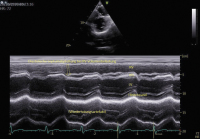

Abbildung 6: Gleiche Patientin wie in Abb. 4 und 5: M-Mode durch den linken Ventrikel (PSAX). Typisch ist bei rechtsventrikulärer Volumenbelastung die diastolische Septumabplattung (Pfeil nach unten). Das Septum müsste sich normalerweise in der Systole nach unten bewegen, tut dies aber in der Diastole.

Keywords: EchoKardiologie